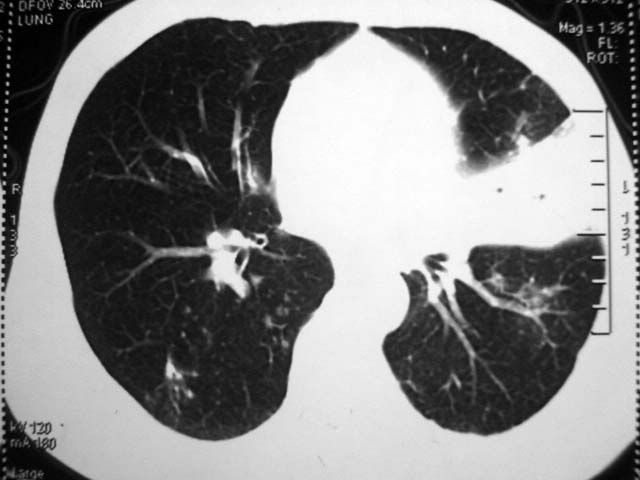

标题: CT17875:肺曲霉菌病?结核? [打印本页]

标题: CT17875:肺曲霉菌病?结核?

男,52岁,发热2月,糖尿病史。

抗结核治疗irpz方案,血糖未治疗,空腹15.9左右。症状无好转,左胸痛。

复查ct

2、双肺见多发片状及结节状高密度影,大多数病灶中心均见“空泡征”。

结果:两肺继发性肺结核并曲霉菌感染。